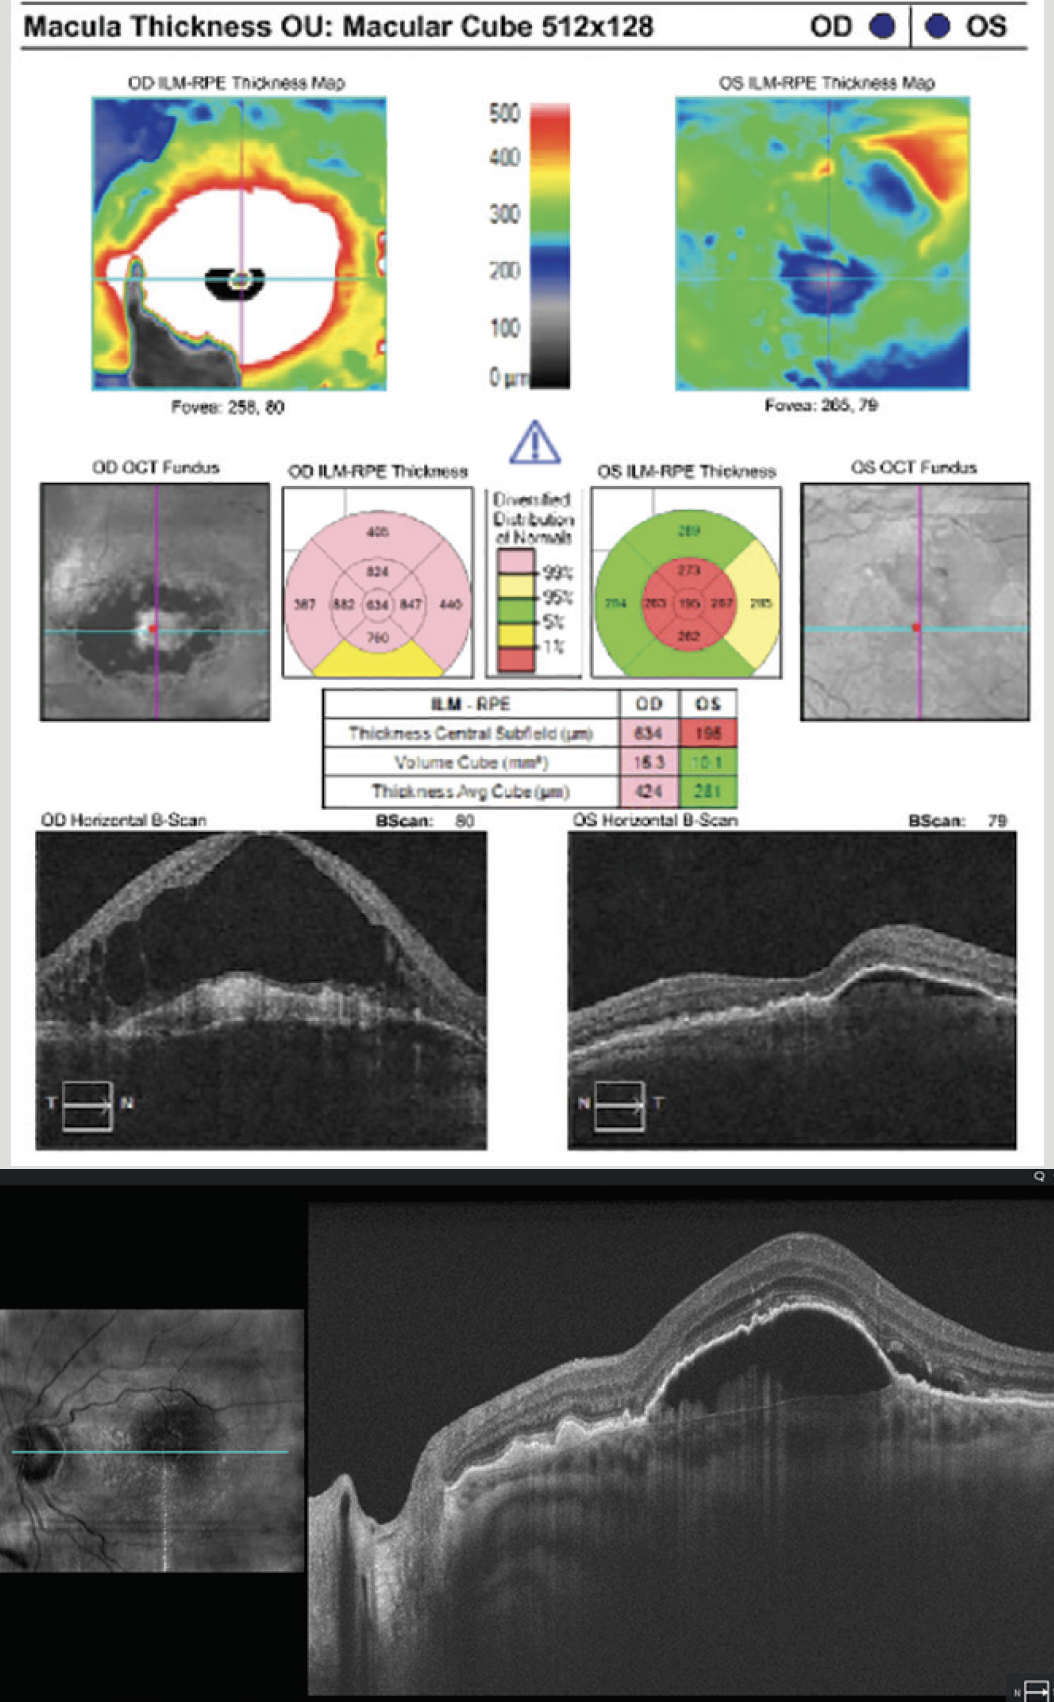

- Continued monthly injections were successful in resolving most of the SRF OS and vision improved to 20/30. Imaging captured hyperreflective material in the PED OS (Figure 2).

Figure 2. Monthly injections were required to achieve modest control of SRF and near resolution of the PED.